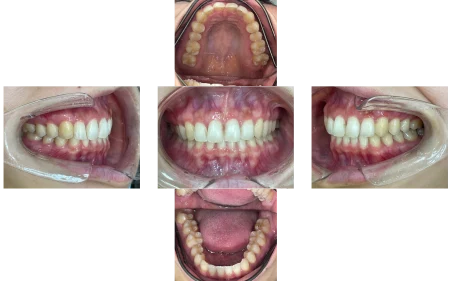

途中半年ほど中断期間がありましたが、上下前歯はきれいな歯並びになりました。

横から見た時の出っ歯感もなくなり、噛み合わせも問題なく、経過は順調です。

患者様からは「歯の捻れが改善されて、気にせず笑えるようになりました」と大変喜んでいただけました。

現在は、ホワイトニングを始められ、メンテナンスでも定期的にご来院いただいています。